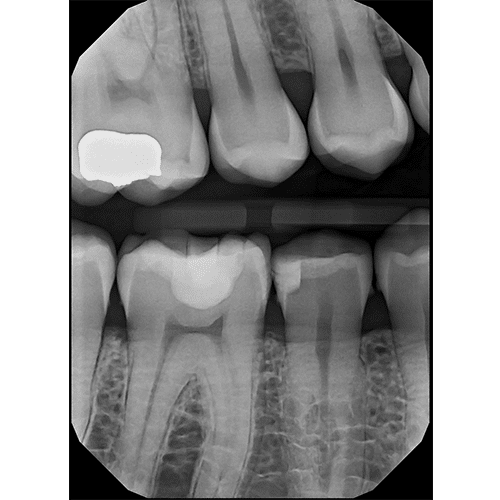

Diagnostic Quality You Can See

Digital X-Ray Sensor

Clio Prime

The elite digital x-ray sensor with EveryShot X-Ray Capture technology. Eliminates under and overexposure, works with any handheld or wall mount x-ray unit. Made in the USA.